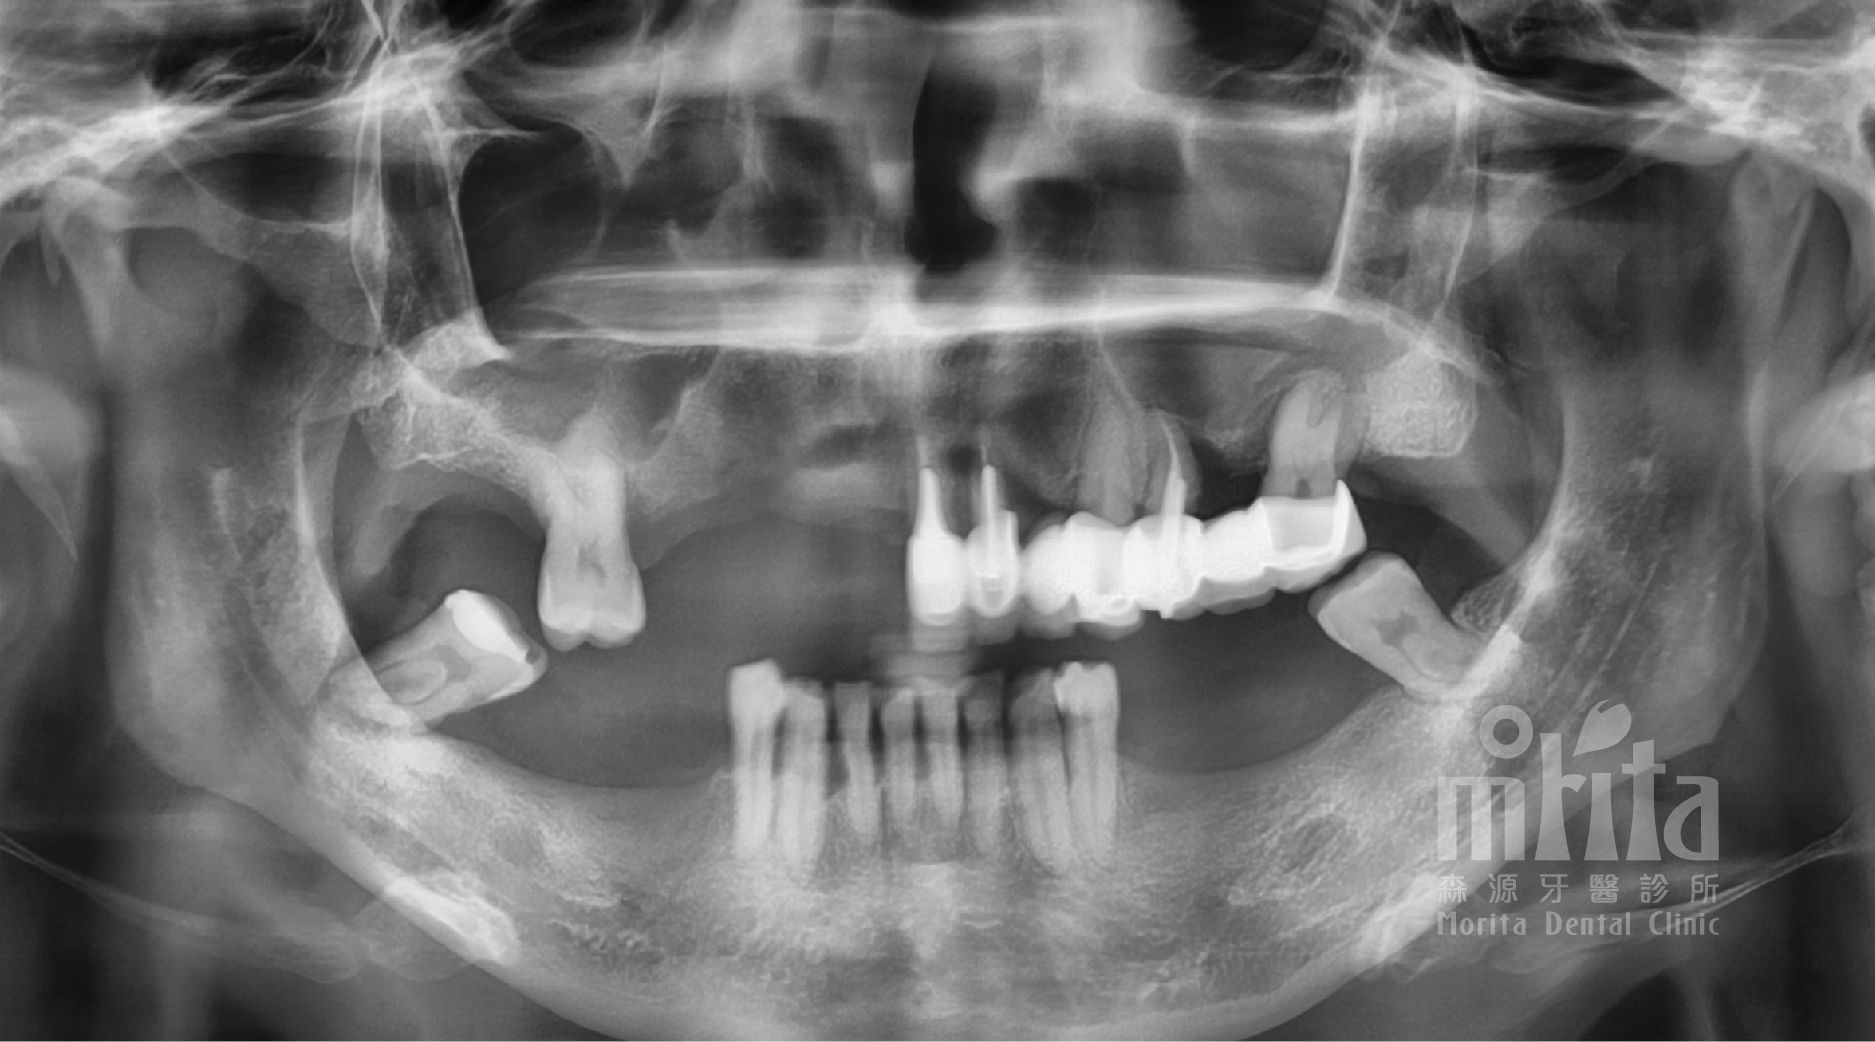

馬小姐來診時表示,因為自己以前疏於照顧牙齒,所以因為嚴重的牙周病而拔除了許多牙齒,造成現在進食困難,並且前牙因為牙周病導致地基不穩定,門牙越來越暴牙。

我們同樣在術前進行了詳細的資料收集與診斷分析,以訂定最適合馬小姐的治療計劃,設計植體如何置放,假牙如何規劃。